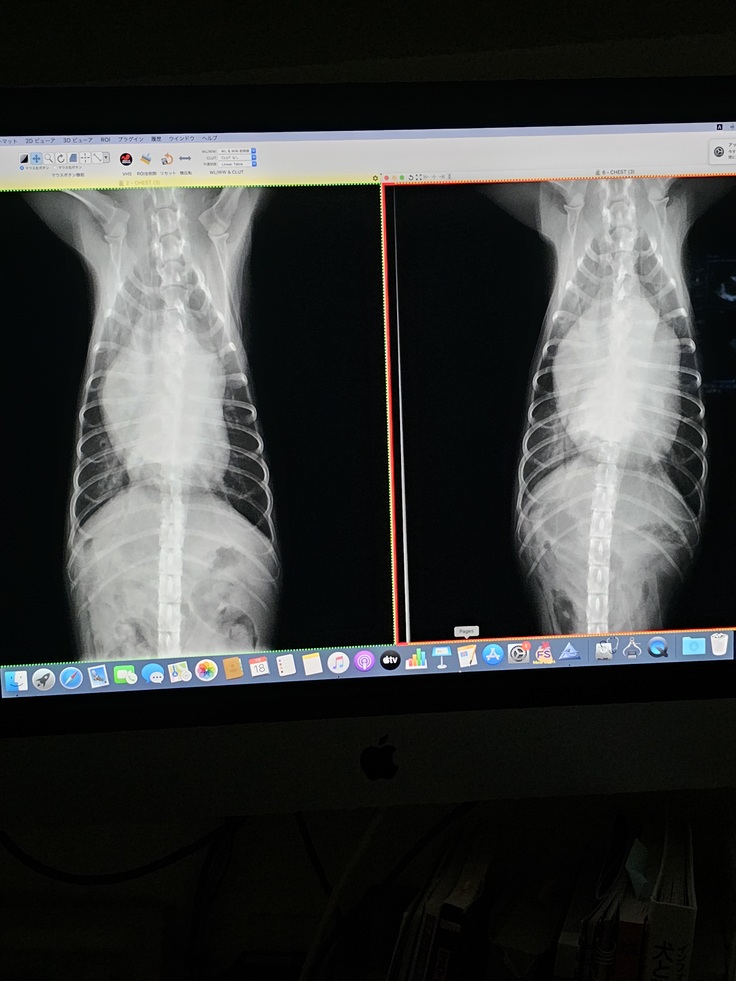

7月18日病院に行きました。

右側が初診の時に撮ったレントゲン。

左側は今日撮ったレントゲンです。

肺に溜まっていたお水も抜け、心臓が少し縮んでいます。

血液検査でも腎臓の数値は正常範囲内。

脱水は起きてます。

そのお陰で心臓が前回より縮んでくれました。

お薬は前回と同じになりました。

今日も利尿剤の注射を打って貰ってます。